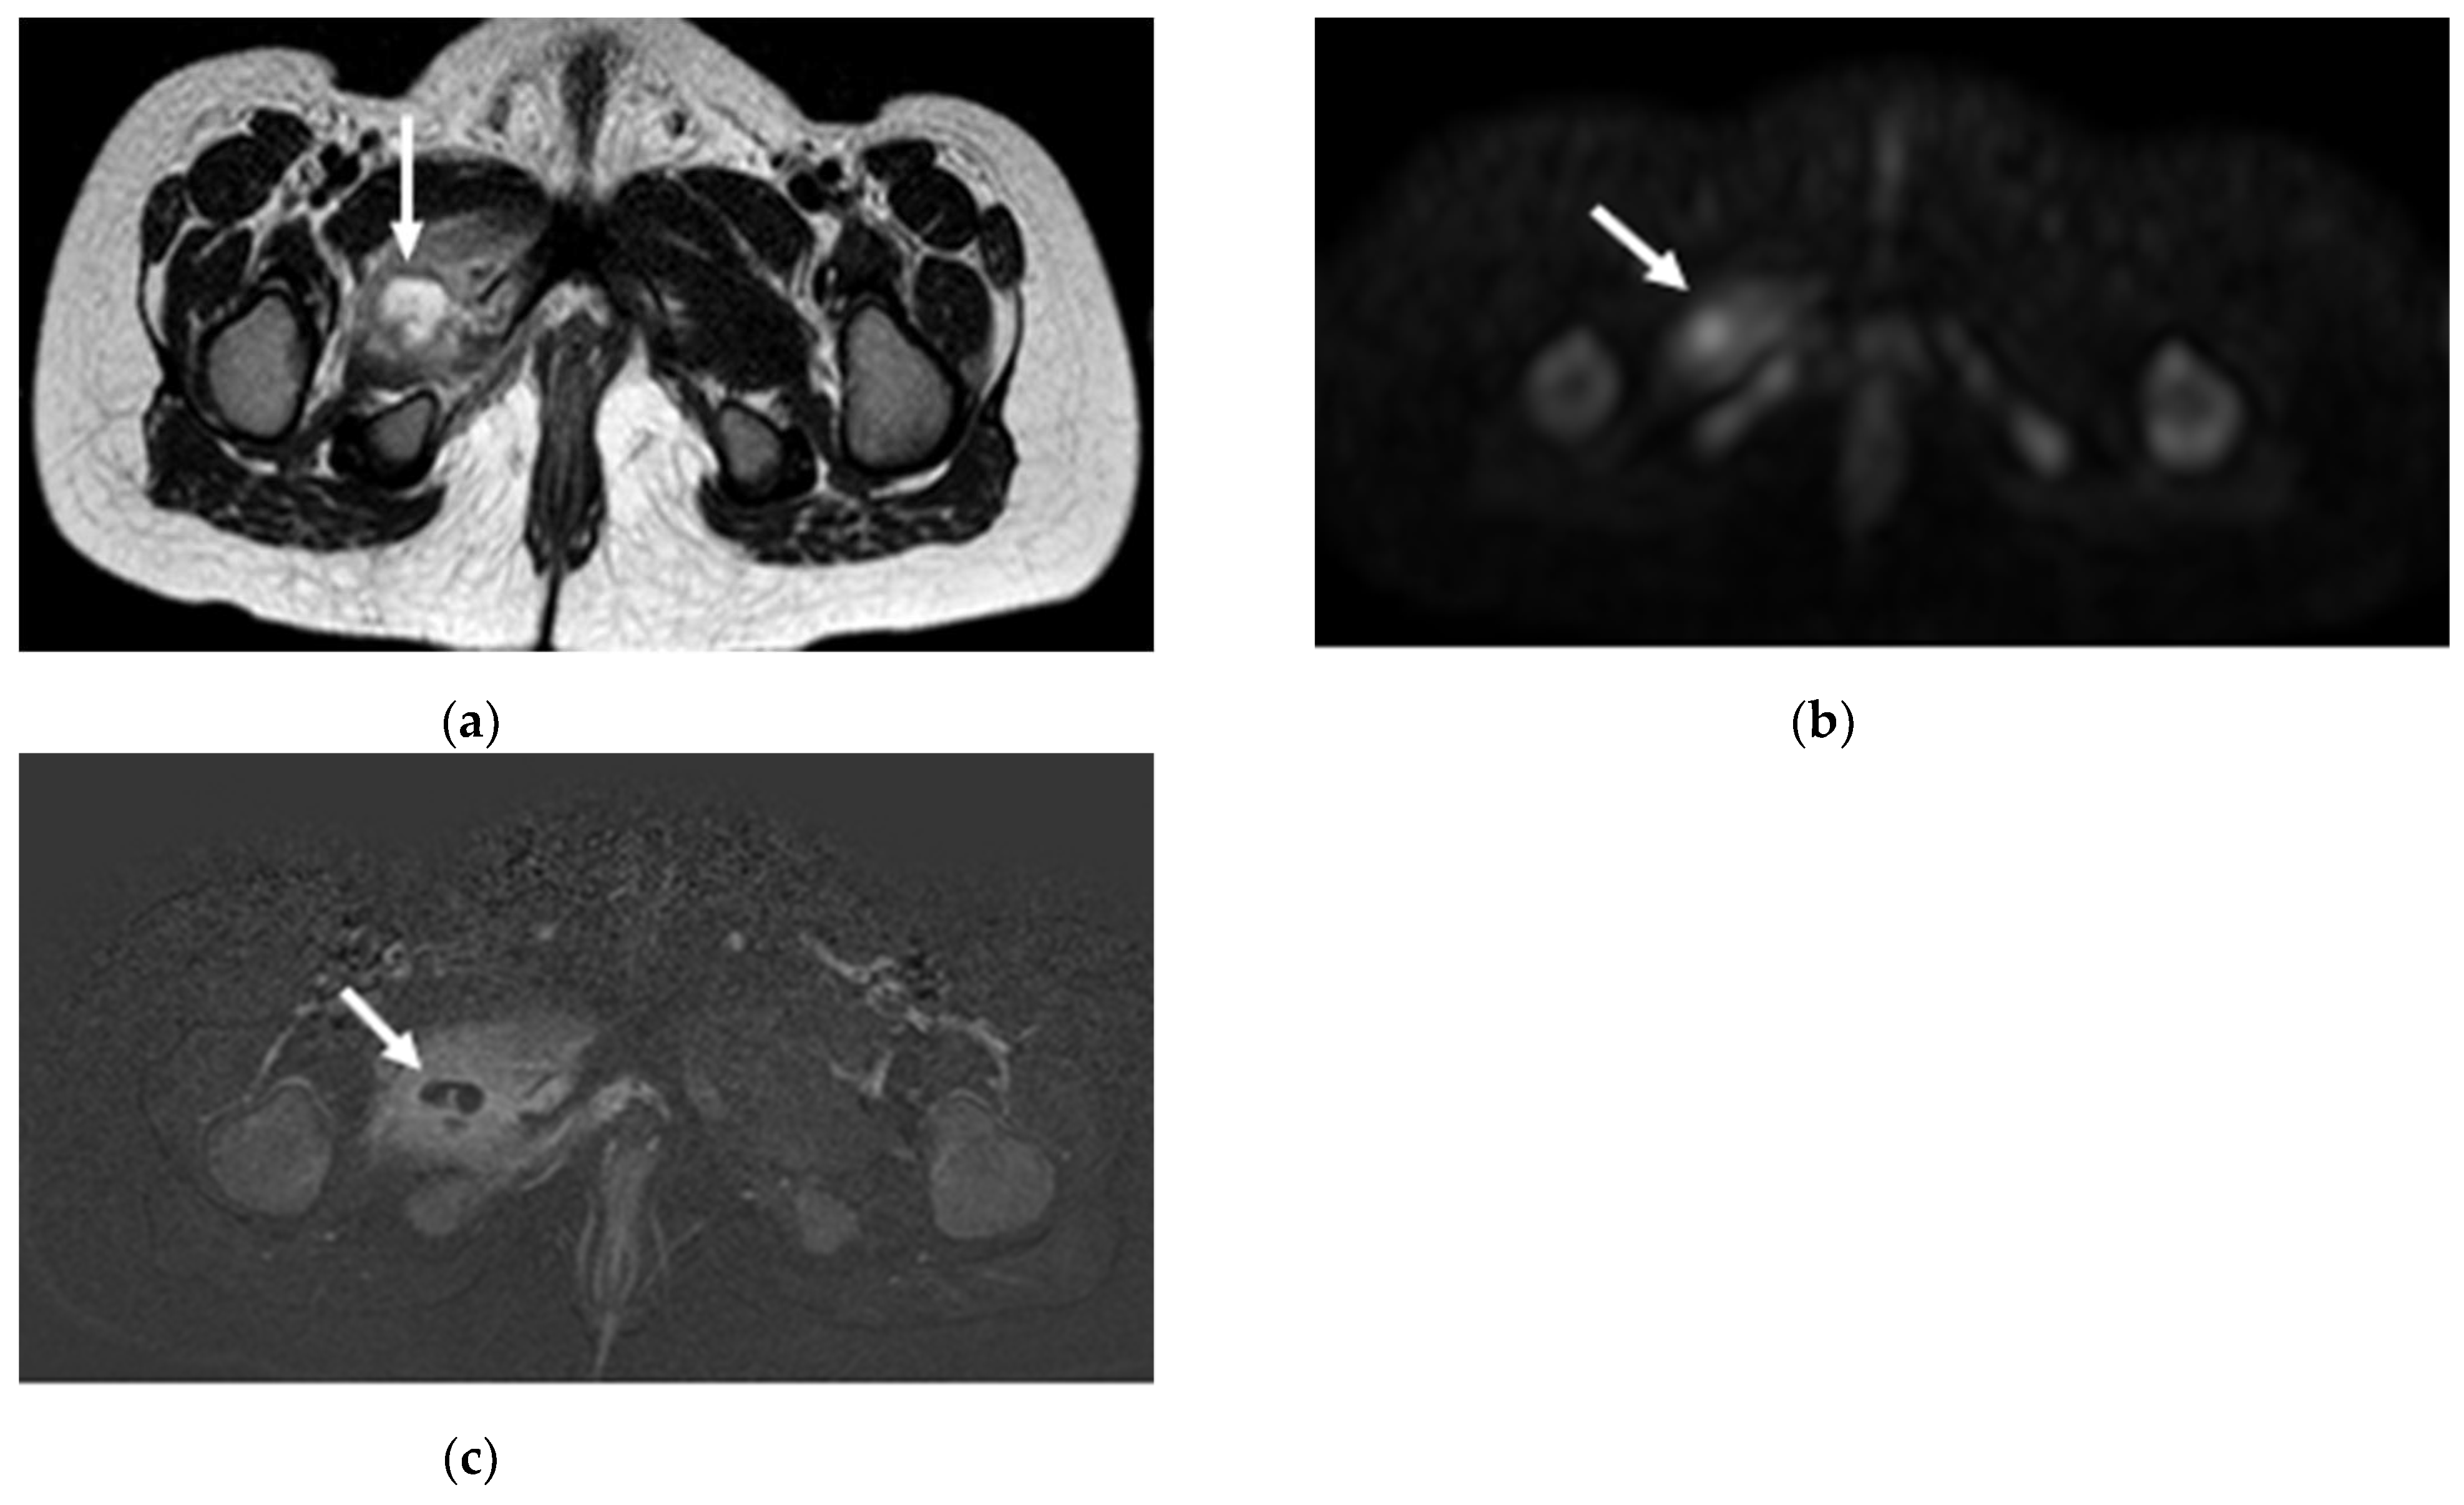

- Khoo, M.M.Y.; Tyler, P.A.; Saifuddin, A.; Padhani, A.R. Diffusion-weighted imaging (DWI) in musculoskeletal MRI: A critical review. Skelet. Radiol. 2011, 40, 665–681. [Google Scholar] [CrossRef]

- Kumar, J.; Khaleel, M.; Boothe, E.; Awdeh, H.; Wadhwa, V.; Chhabra, A. Role of Diffusion Weighted Imaging in Musculoskeletal Infections: Current Perspectives. Eur. Radiol. 2016, 27, 414–423. [Google Scholar] [CrossRef]